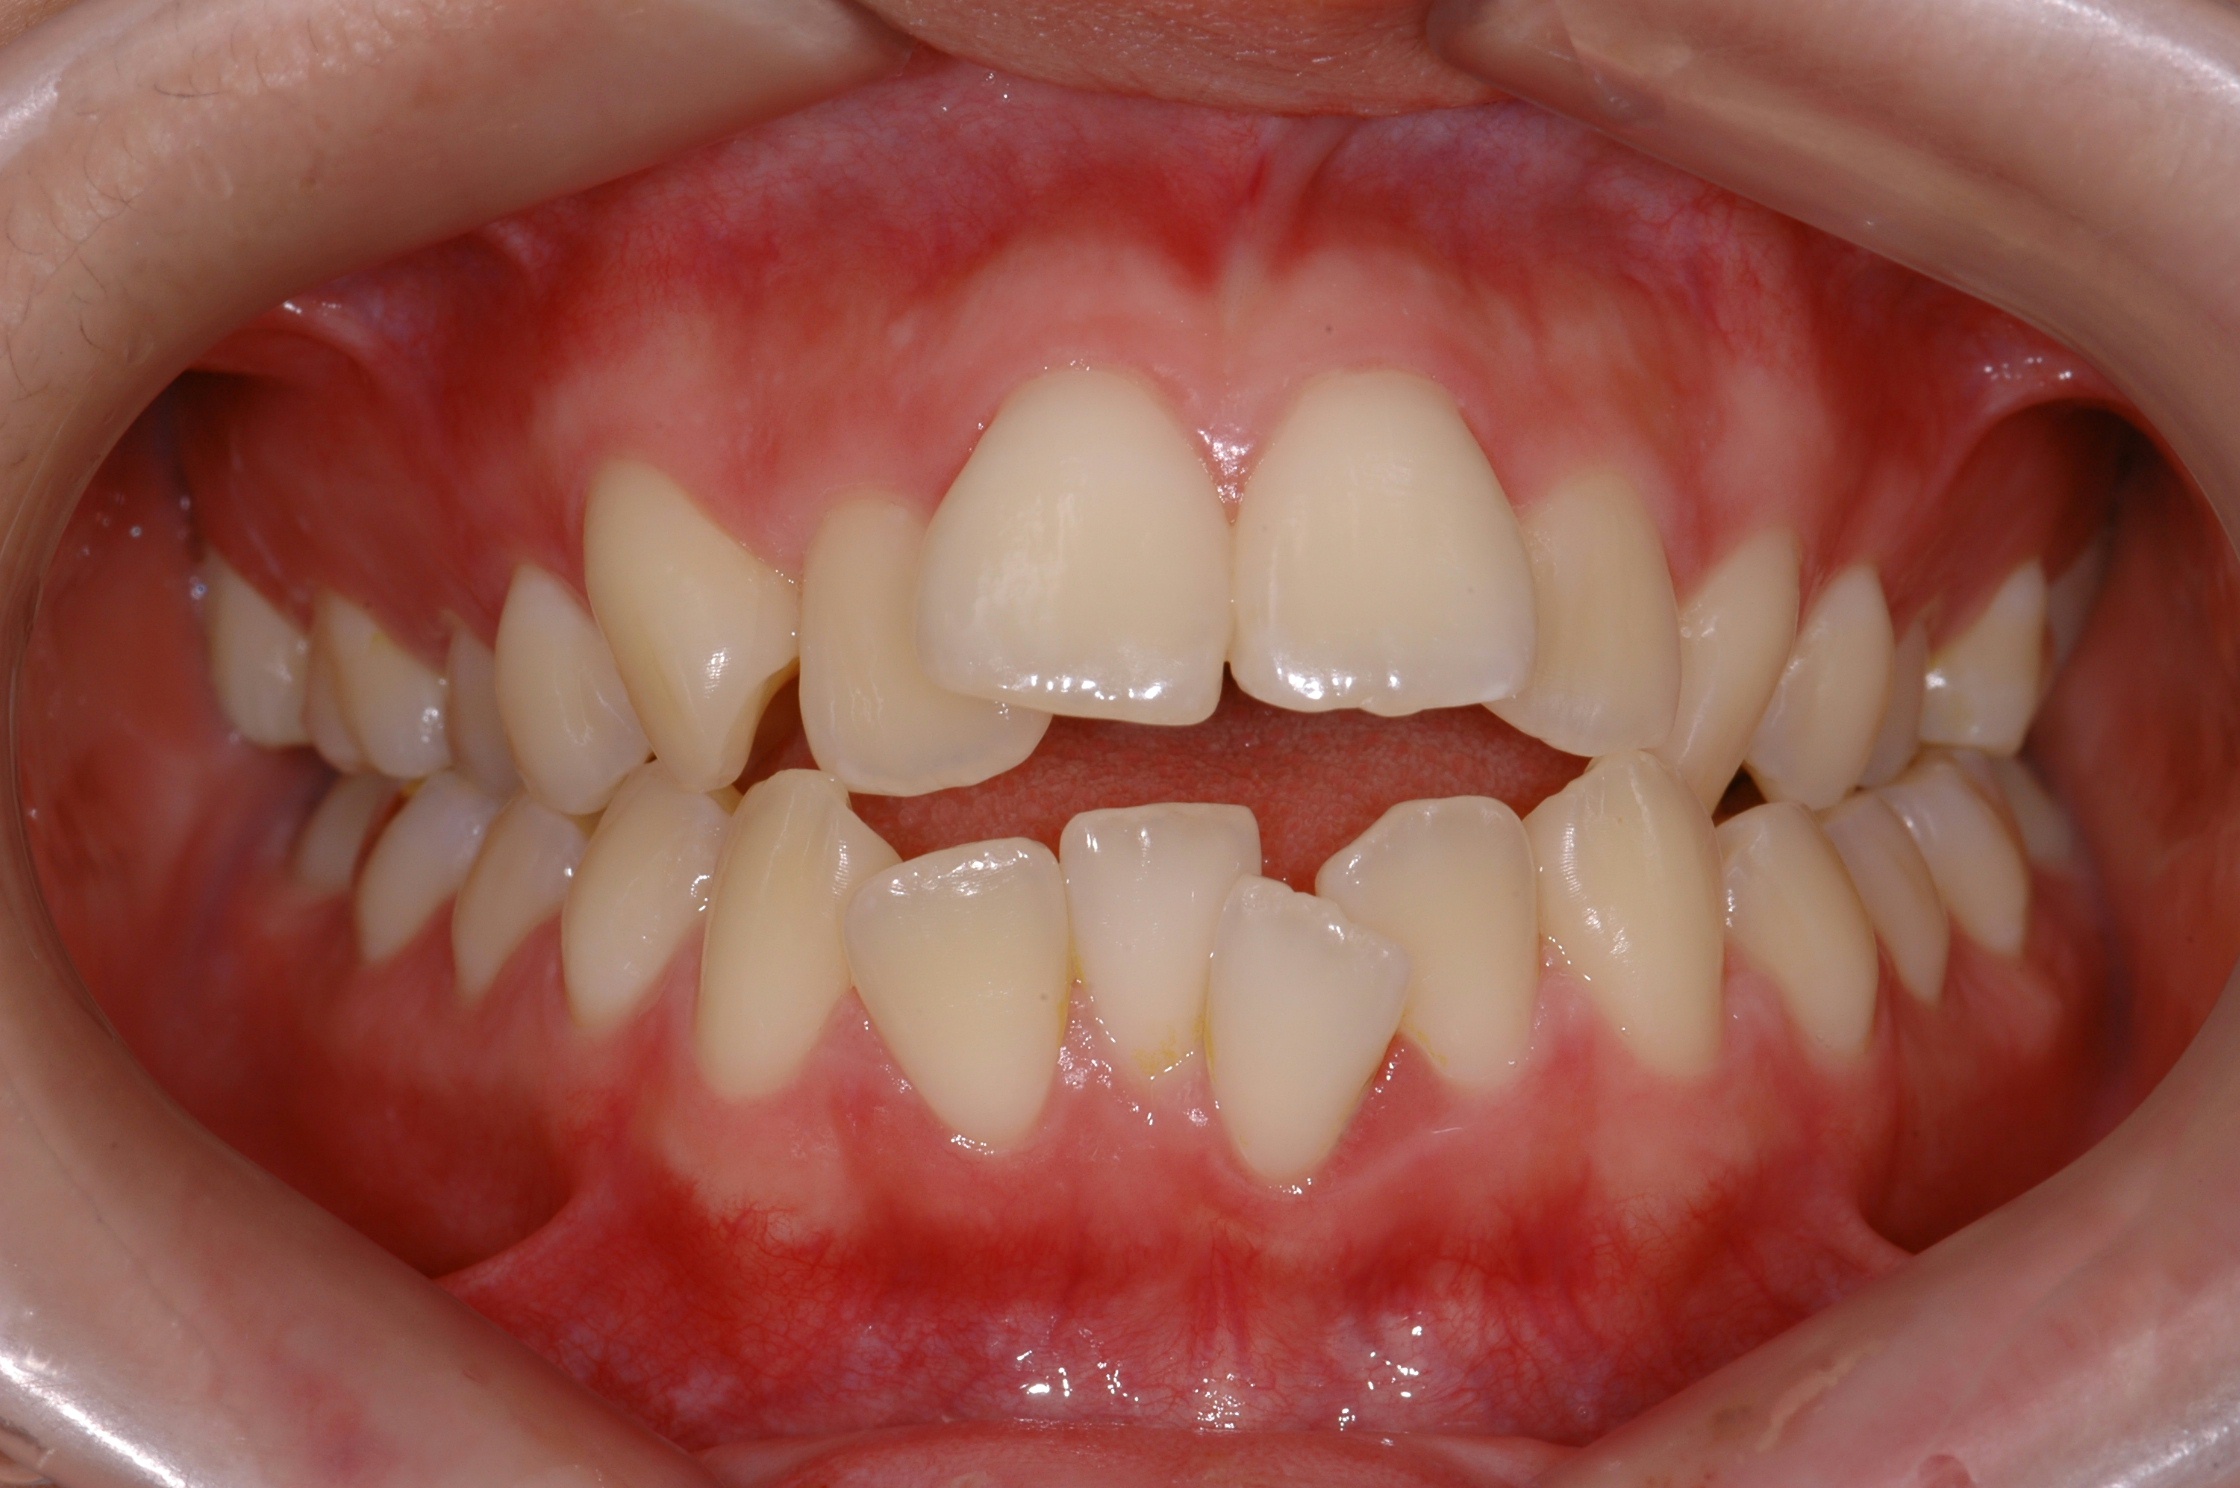

치료 전 사진입니다.